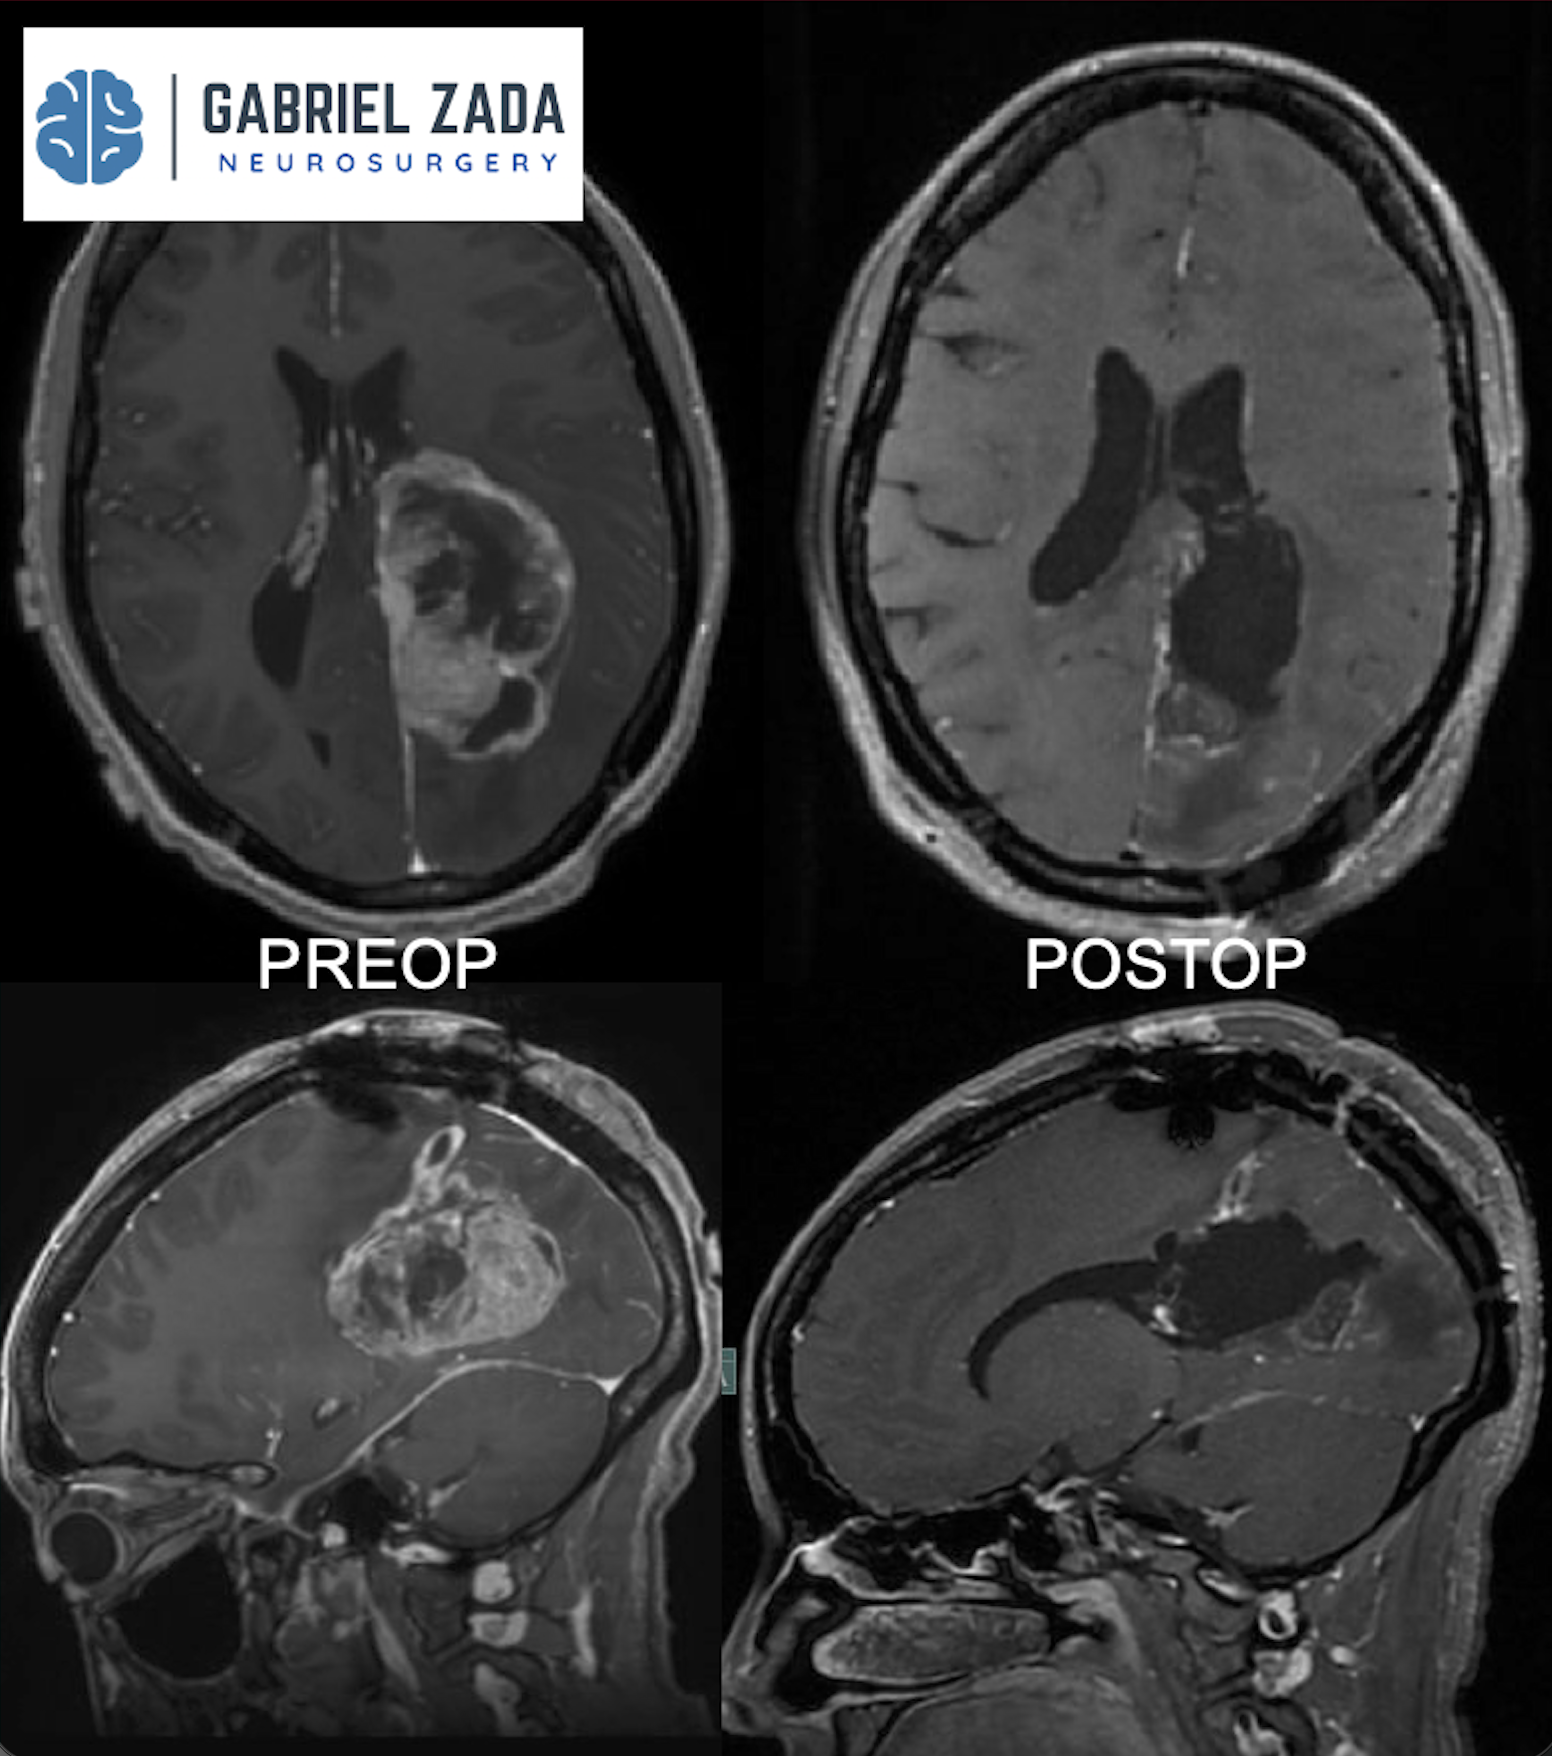

Explore this comprehensive gallery featuring pre‑ and post‑operative imaging of patients with skull‑base tumors treated by Gabriel Zada, MD, MS, FAANS, FACS. These cases highlight Dr. Zada’s expertise in advanced neurosurgical techniques and outcomes.

*Representative cases shown for educational purposes. All images de-identified. Individual results vary.